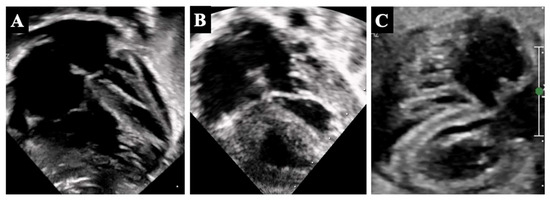

3. Borderline Left Ventricle: Predictors of Biventricular Repair

5.1. Borderline Left Ventricle